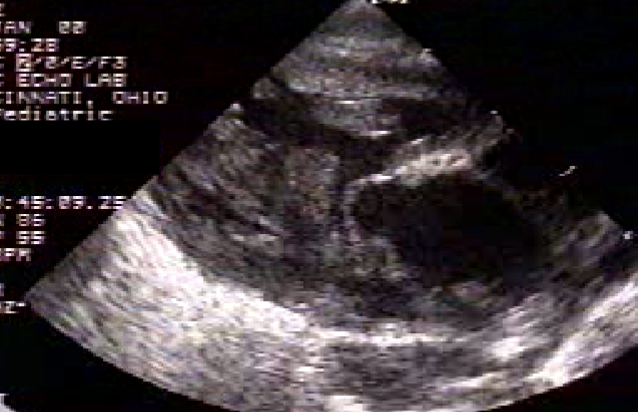

TOF 2D findings:

PLAX

overriding Ao

VSD

RVH

PSAX

VSD (mid)

PS/RVOTO (base)